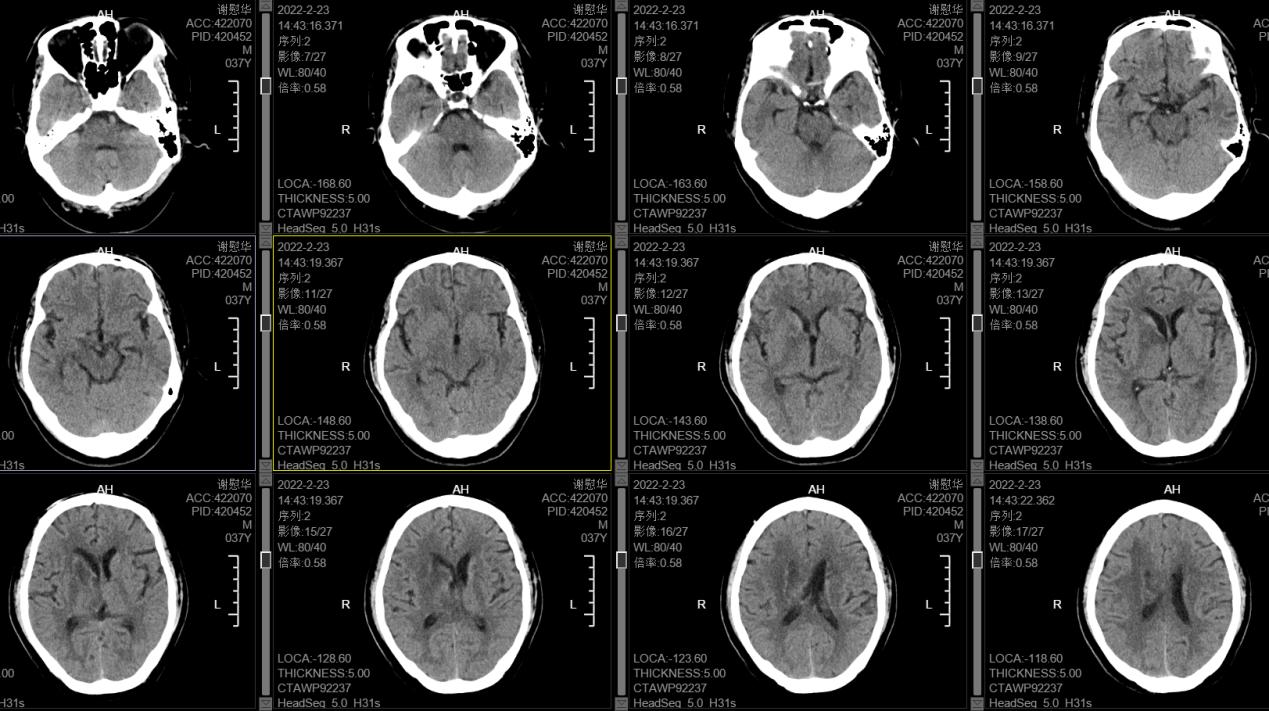

在王智勇主任及神经外科团队的相互配合下,成功为阿志施行三维定向置管微创手术,术后第二天,阿志逐渐恢复神志,经过持续引流和注射药物溶解淤血块等综合治疗,他的病情也逐步稳定好转,颅内出血基本吸收,可自行站立,左侧肢体力量也逐渐恢复到发病前状态并顺利出院。近日复诊时,阿志病情基本康复,未遗留明显的后遗症。

经治疗后的头颅CT片(白色的血肿已清除)